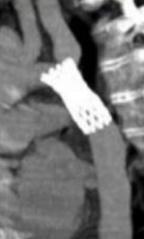

Traitement

- Stent